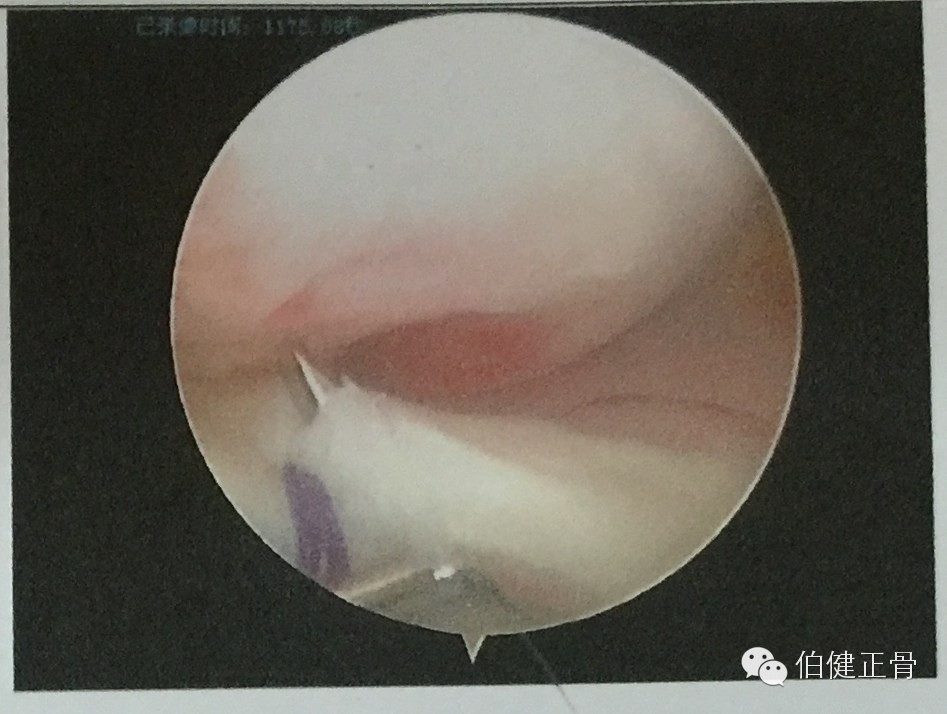

第一步,关节镜检查,可见骨块上翻移位:

第二步,穿线于骨块上方的韧带,绑拉骨块:

牵拉缝线可完美复位: